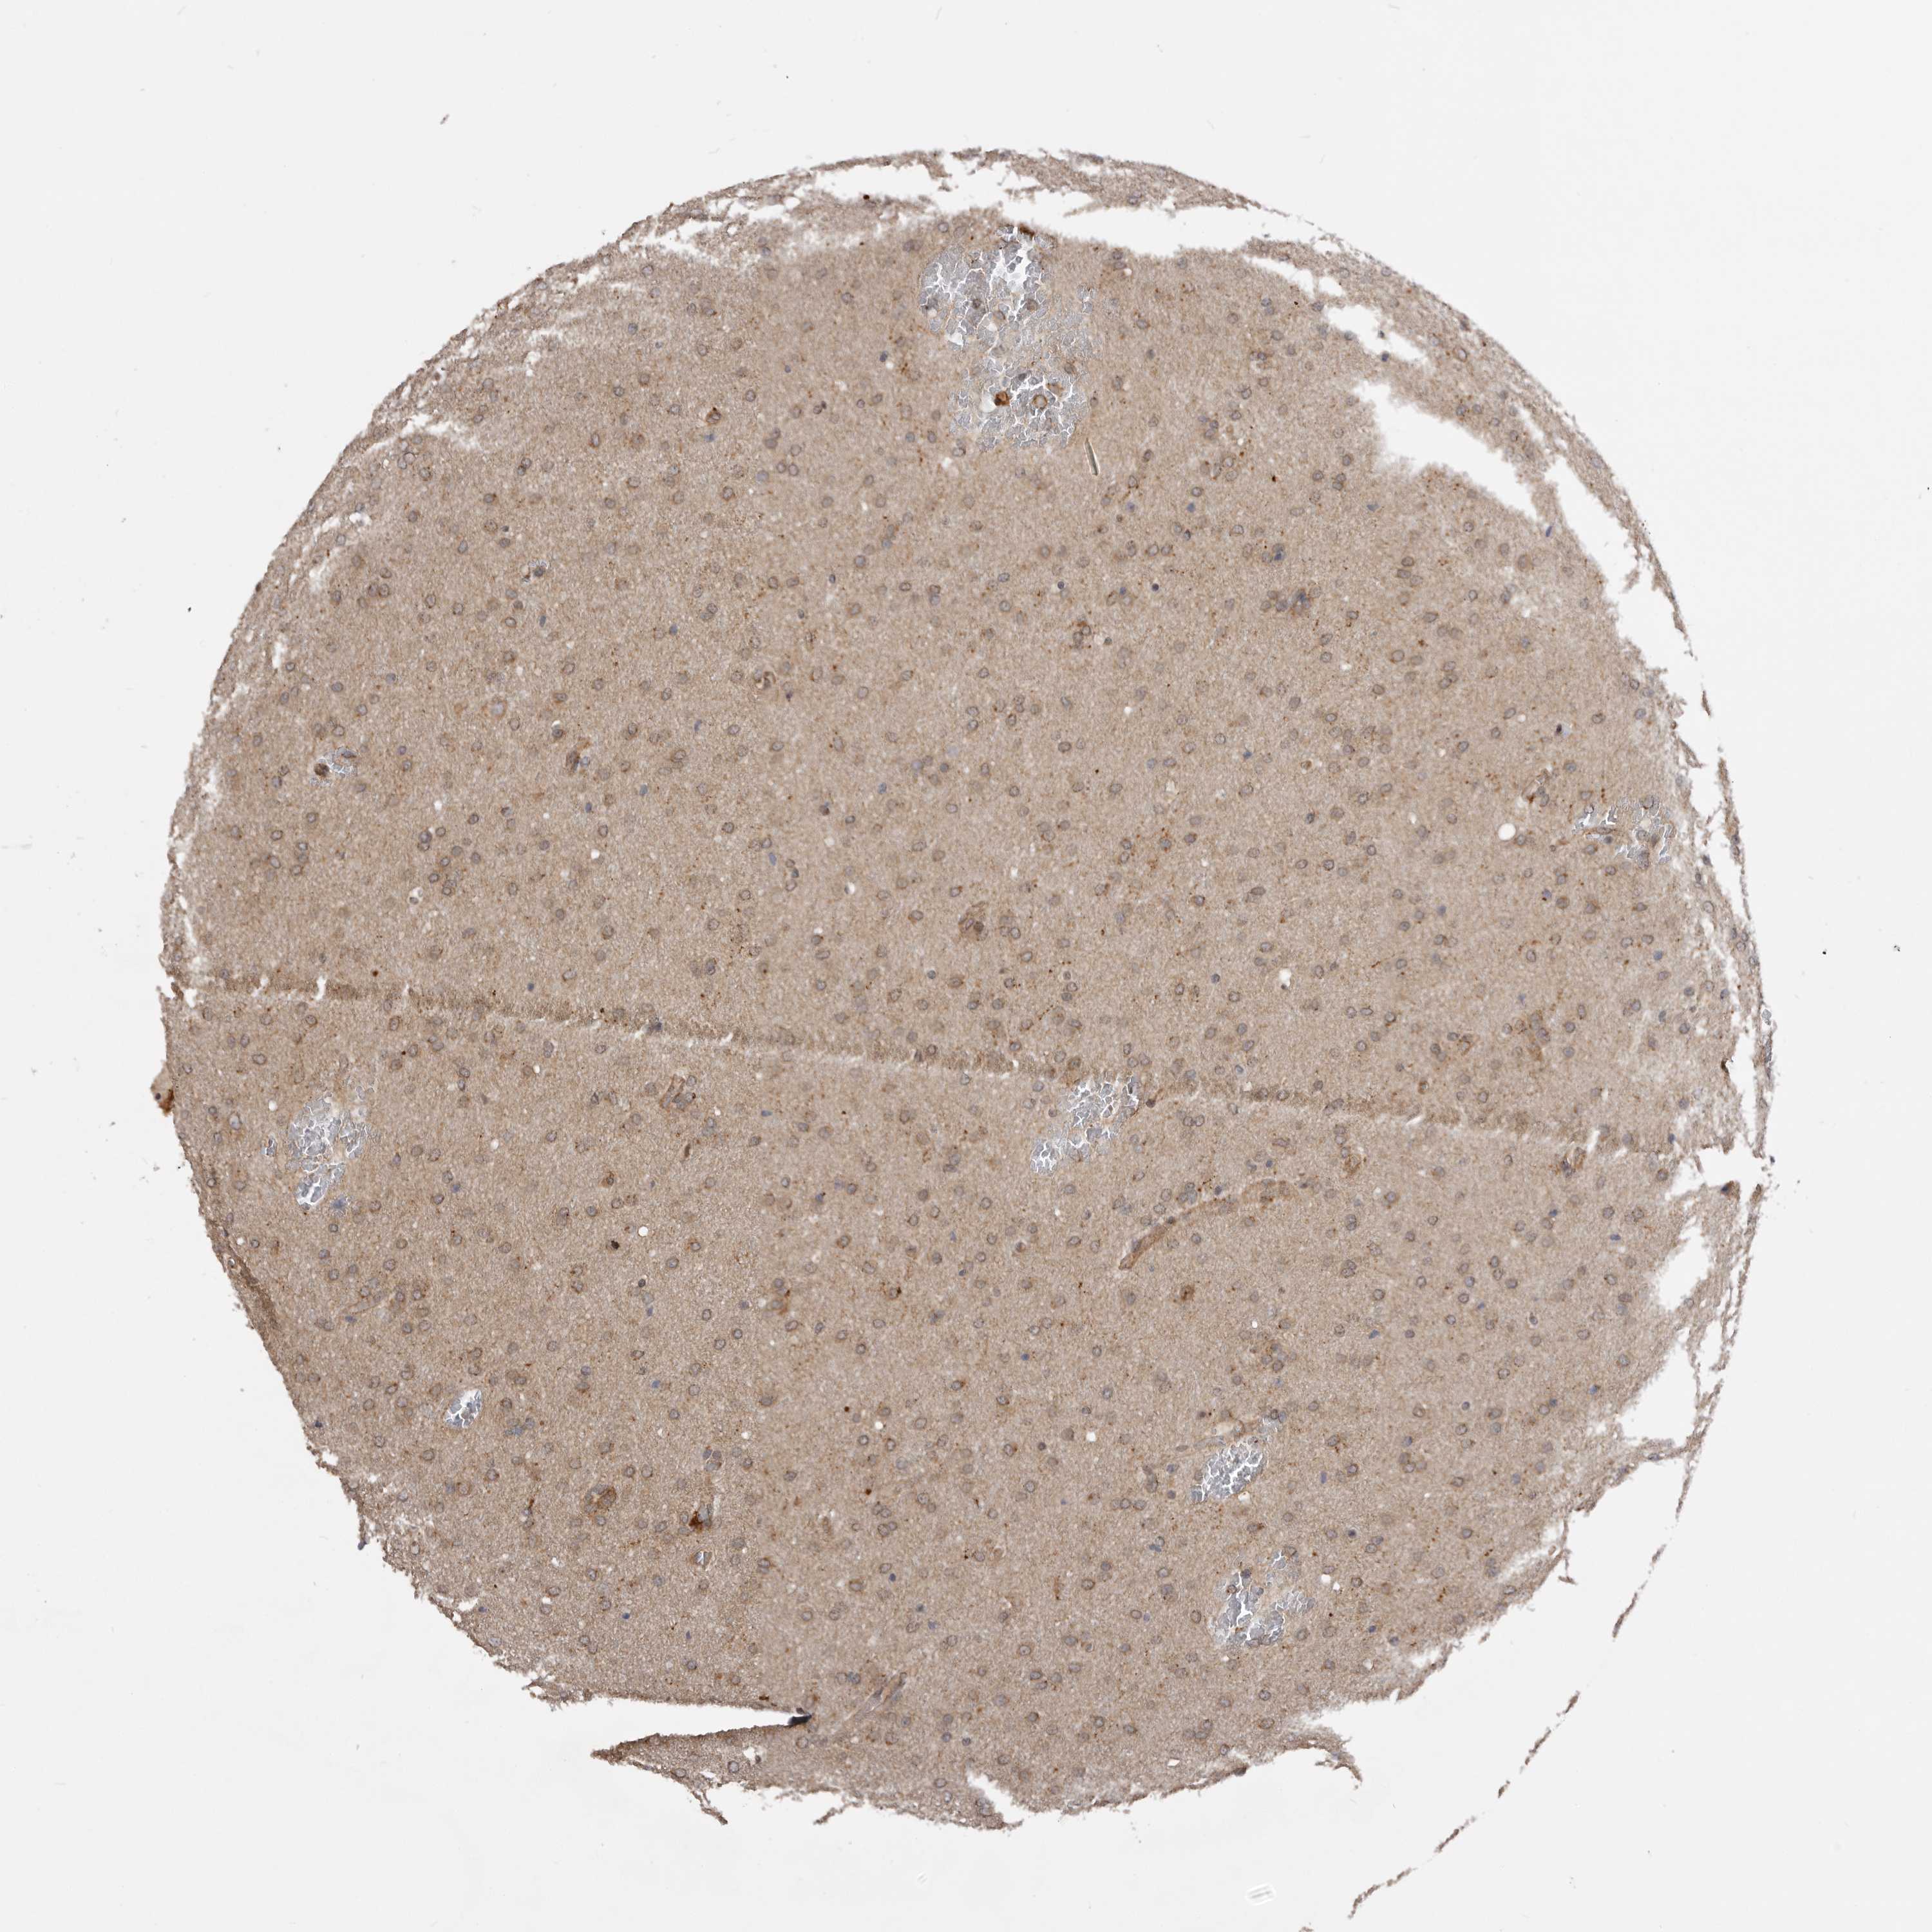

GLIOMA - Protein expressioni

A mouse-over function shows sample information and annotation data. Click on an image to view it in a full screen mode. Samples can be filtered based on level of antibody staining by selecting one or several of the following categories: high, medium, low and not detected. The assay and annotation is described here.

Note that samples used for immunohistochemistry by the Human Protein Atlas do not correspond to samples in the TCGA dataset.

Antibody stainingi

Antibody staining in the annotated cell types in the current human tissue is reported as not detected, low, medium, or high, based on conventional immunohistochemistry profiling in selected tissues. This score is based on the combination of the staining intensity and fraction of stained cells.

Each image is clickable and will lead to virtual microscopy that enables deeper exploration of all samples and also displays staining intensity scores, fraction scores and subcellular localization as well as patient and tissue information for each sample.

Antibody HPA024358

Staining

High

Medium

Low

Not detected

Intensity

Strong

Moderate

Weak

Negative

Quantity

>75%

75%-25%

<25%

None

Location

Nuclear

Cytoplasmic/membranous

Cytoplasmic/membranous,nuclear

Glioma, malignant, High grade

Glioma, malignant, Low grade